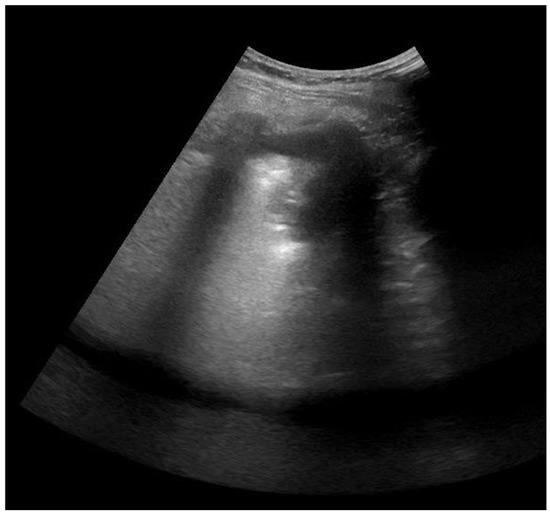

2.4. Lung Ultrasonography and Score Assessment

| Interstitial Edema (B1 pattern) | 35 (92%) | 23 (61%) |

| Alveolar Edema (B2 pattern) | 31 (82%) | 16 (42%) |

| Consolidation (C) | 11 (29%) | 4 (11%) |